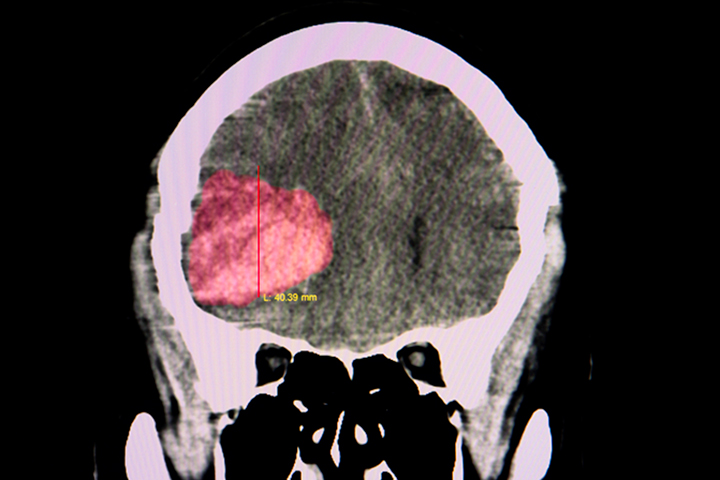

Terapia antiplaquetaria después de un accidente cerebrovascular por hemorragia intracerebral